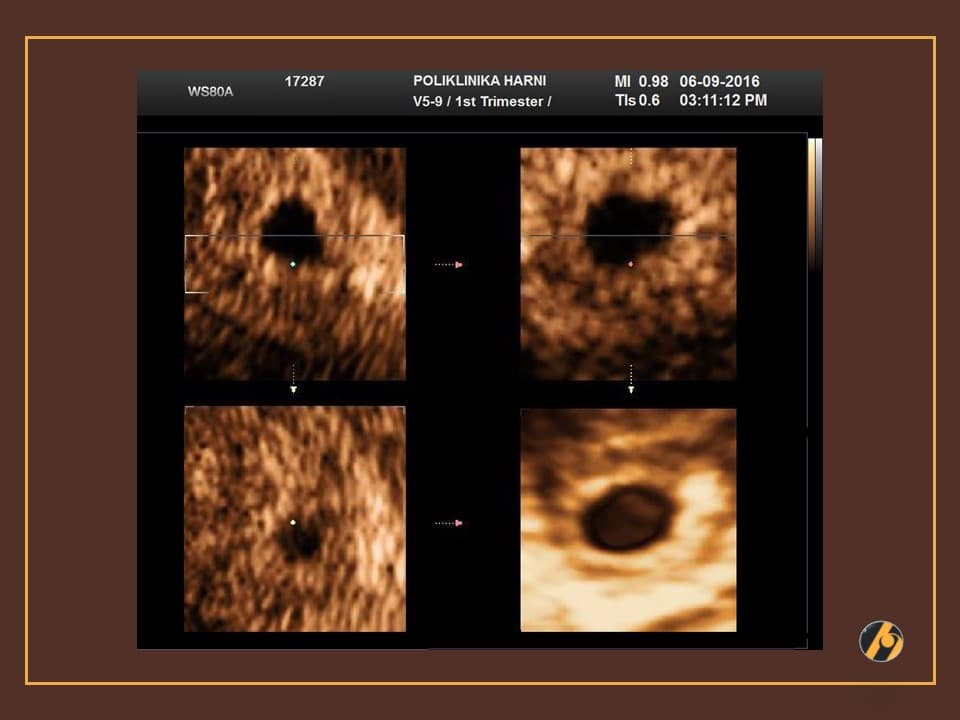

Carnegie stadij 6 odlikuje proliferacija i migracija stanica epiblasta u pravcu središnje linije embrionalnog diska i nastanak "primitivne pruge", koja raste u duljinu dok ne dosegne polovicu embrionalnog diska. Primitivna pruga je mjesto u koje poniru stanice koje migriraju iz lateralnih dijelova diska, a koje će formirati mezoblast i endoblast. Na ovaj način nastaje trilaminarni embrionalni disk, a ovo je vrijeme kada možemo dobiti i prve ultrazvučne slike u trudnoći.

Glavni kriterij za Carnegie stadij 7 je pojava notokordalnog nastavka neposredno rostralno u odnosu na primitivni čvor i prugu. Embrionalni disk je u pravilu okrugao, ovalan ili kruškolik. Stanice koje poniru u predjelu primitivnog čvora migriraju uzduž medijalne linije kranijalno i formiraju notokordalni nastavak, a ovaj proces se može usporediti s klizanjem prstiju u rukavicu. Na ultrazvučnim slikama iz ovog razdoblja prepoznaju se gestacijska i žumanjčana vreća.